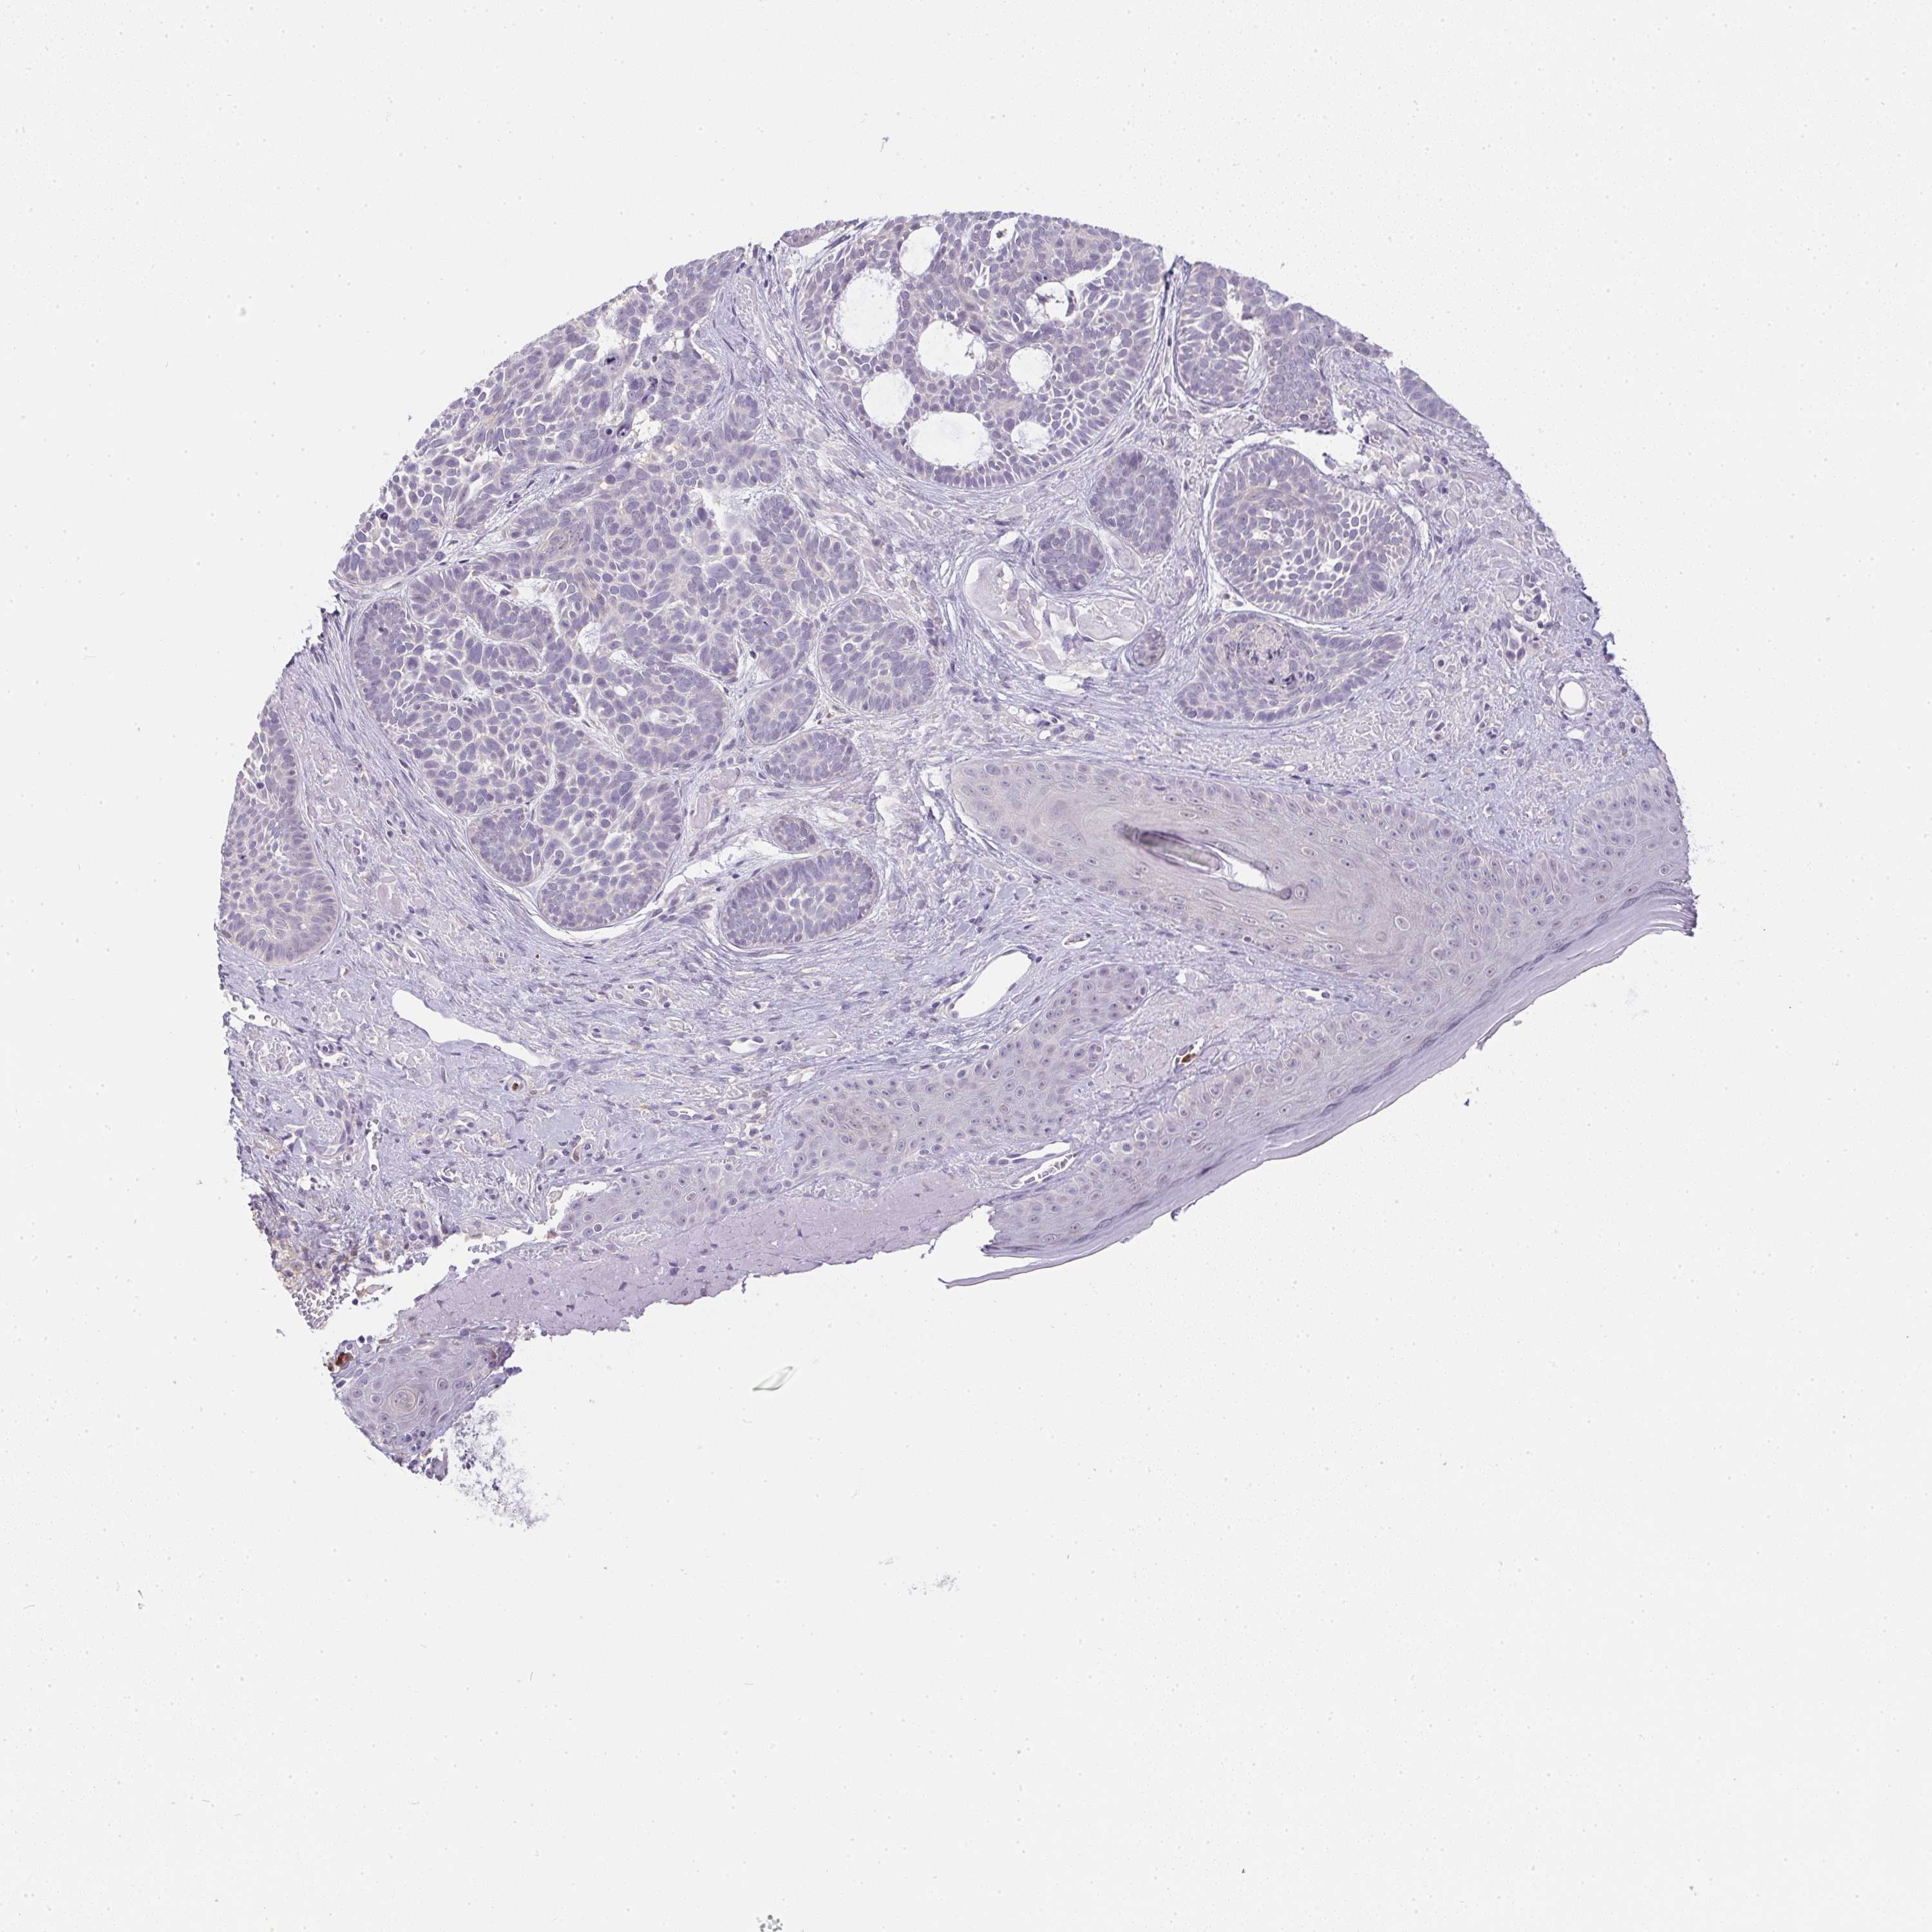

Basal cell and squamous cell cancer

SKIN CANCER - Protein expressioni

A mouse-over function shows sample information and annotation data. Click on an image to view it in a full screen mode. Samples can be filtered based on level of antibody staining by selecting one or several of the following categories: high, medium, low and not detected. The assay and annotation is described here.

Antibody stainingi

Antibody staining in the annotated cell types in the current human tissue is reported as not detected, low, medium, or high, based on conventional immunohistochemistry profiling in selected tissues. This score is based on the combination of the staining intensity and fraction of stained cells.

Each image is clickable and will lead to virtual microscopy that enables deeper exploration of all samples and also displays staining intensity scores, fraction scores and subcellular localization as well as patient and tissue information for each sample.

Antibody HPA041445

Staining

High

Medium

Low

Not detected

Intensity

Strong

Moderate

Weak

Negative

Quantity

>75%

75%-25%

<25%

None

Location

Nuclear

Cytoplasmic/membranous

Cytoplasmic/membranous,nuclear

Basal cell carcinoma

Squamous cell carcinoma, NOS